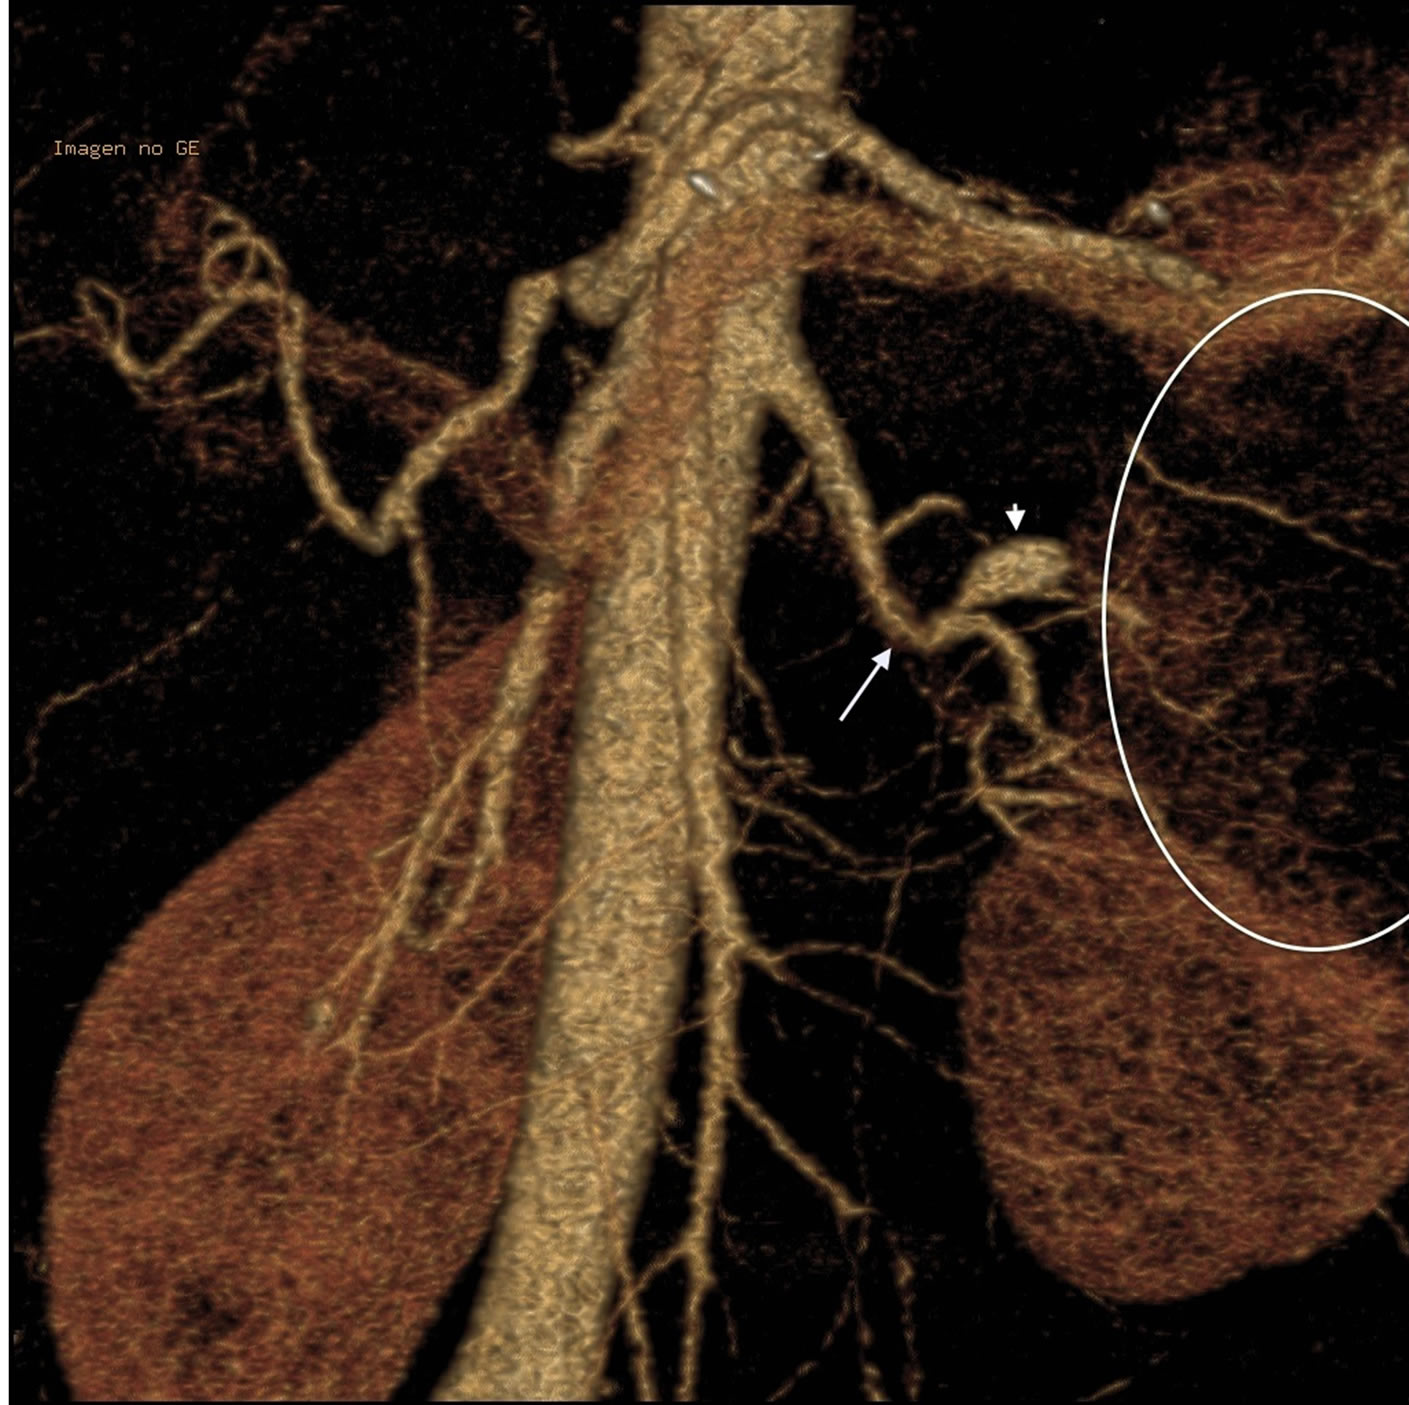

Ten years after delivery, the patient suddenly developed severe pain in the left lumbar fossa radiating to the abdomen lasting for about 36 hours. This was initially attributed to renal colic. Six days later the pain recurred and was now localized to the epigastric and mesogastric regions. This prompted hospital admission. The pain improved with bowel rest, analgesics and treatment with omeprazole. Laboratory blood tests revealed a moderate elevation in Lactate dehydrogenase and hematuria. Radiological studies were performed 11 and 21 days after the onset of symptoms. These showed a left renal infarct and the vascular abnormalities illustrated and described in Figures 1 to 5. On the bases of the laboratory findings and the renal radiologic studies a diagnosis a left renal infarct was established and a diagnosis of SAM was made supported by the intestinal angiographic findings.

Figure 2. 3D CT reconstruction of abdominal aorta showing mild stenosis before bifurcation of the left renal artery (oblique arrow), an aneurysm of a superior polar branch (arrow head) and a left kidney superior pole infarct (ellipse).

The histological and angiographic findings and clinical symptoms in the current case are a classic representation of reparative phase SAM converted to FMD. An assortment of arterial lesions detected both histologically and radiologically is an important diagnostic feature of both injurious and reparative phase SAM. This variety is created by the varying intensities of the two different arterial injurious lesions, their asynchronous maturation, degree and sites of florid repair and segmental distribution [3]. This case illustrates the varying types of lesions typifying reparative phase SAM. These are medial-adventitial tears repaired by granulation tissue that serves as both sites and sources of dissecting and mural hematomas (Figures 8-10). Prior studies of SAM have shown that these lesions are initiated from hemorrhage in the granulation tissue filling the adventitial-medial separation plane rather than from intimal tears [1,3] and as this case illustrates, by the unsatisfactory stent attempt, this bleeding can be traumatically induced. We suspect that the cuff surrounding the celiac axis (Figure 1) represents a mural hematoma possibly partially or totally filled with granulation tissue. The second lesion is sequela aneurysms that are well repaired by granulation tissue that forms plaques over adjacent intact arterial intima and may bedeck surviving medial islands (Figure 8). These frequently grossly appear as large fusiform aneurysms (Figure 2) formed by two or more adjacent microscopic aneurysms created by the segmental distribution of SAM’s gaps. The latter fashions the saw-toothed appearance frequently found in medial FMD. The third lesion is the occurrence of medial granulation tissue with fibrosis repairing areas of mediolysis Figures 9 and 11). This change always commences in the outer media and may extend inwardly to involve some or all of the inner media. It is often patchy because of the survival of muscle cells in zones of mediolysis. Arterial stenosis, the forth lesion, is cause by the aforementioned lesions and reparative intimal plaques (Figures 3, 5 and 11). The fifth lesion is the formation of thrombi formed in both the aneurysms and pseudo-lumens of dissecting hematomas with thrombo-embolization developing distal to these lesions.